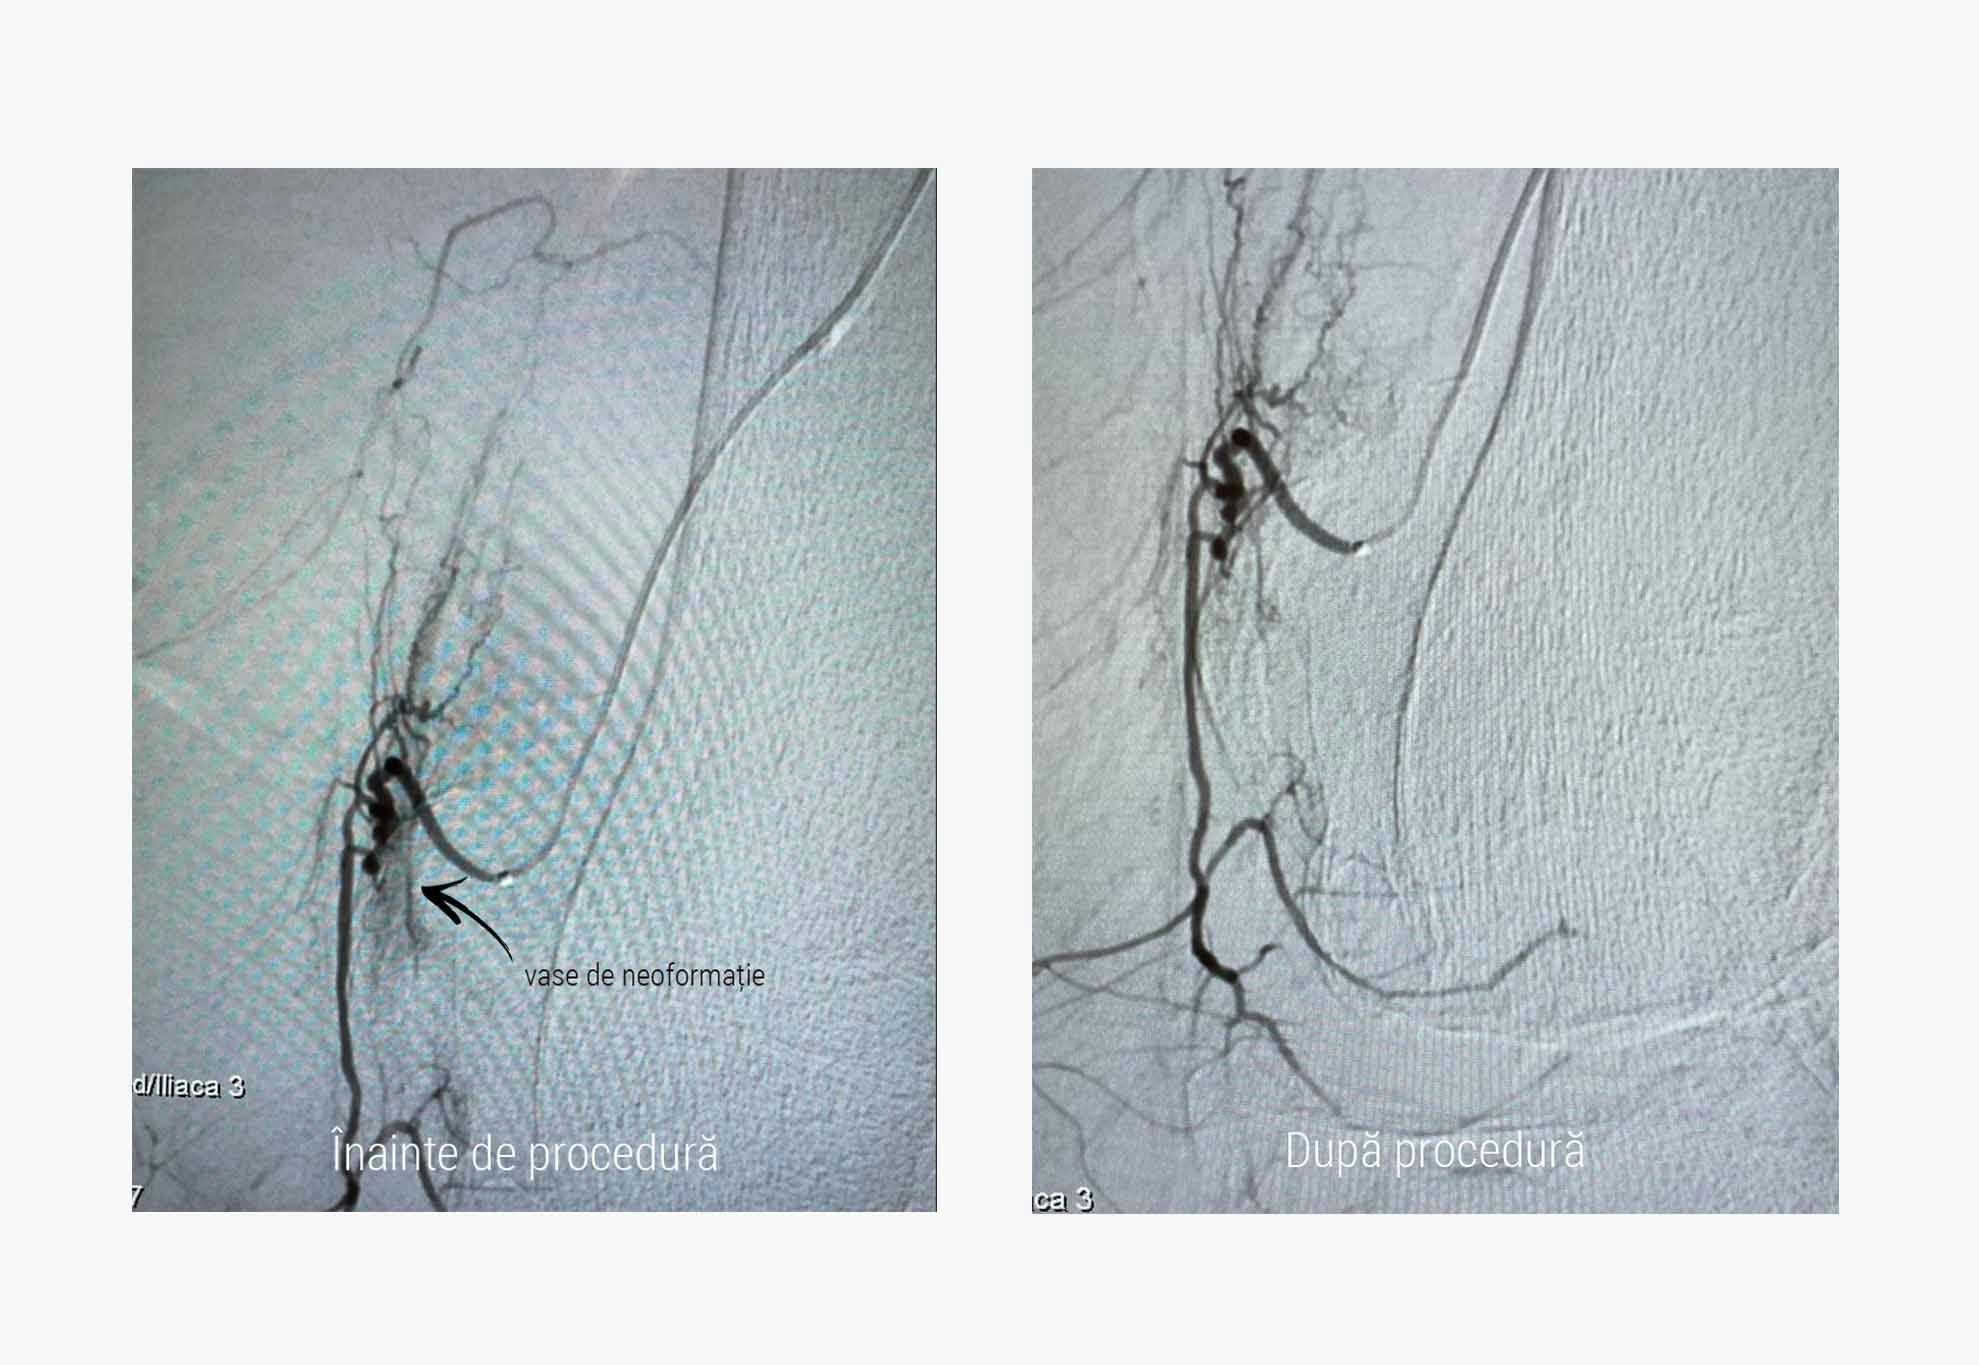

Embolizarea periarticulară presupune injectarea de microparticule biocompatibile la nivelul vaselor de neoformație responsabile pentru producerea și întreținerea durerilor articulare de la nivelul genunchiului, umărului sau cotului.

Astfel, dr. Florin Bloj a efectuat procedura de embolizare periarticulară: la nivelul arterei brahiale s-a efectuat puncția milimetrică prin care au fost ghidate catetere prin artera femurală superficială dreaptă și respectiv, artera femurală superficială stângă până deasupra genunchiului. Aici, prin injectarea substanței de contrast, au fost vizualizate arterele geniculare responsabile de irigarea articulației genunchiului. Odată identificate zonele de hiperemie, respectiv zonele de neoformație vasculară, acestea au fost embolizate cu particule de 100 de microni.

Ca metodă de tratament, embolizarea periarticulară poate fi efectuată prin două alternative: în funcție de caz, medicul poate opta pentru închiderea vaselor de neoformație cu particule inerte care acționează ca un dop sau cu imipenem/ cilastatin, un antibiotic care în substanța de contrast cristalizează și formează particule de 75 microni, cu rol mecanic și totodată, antiinflamator.

Vasele normale ale articulației rămân neatinse, circulația sângelui la acest nivel nu este restricționată în niciun fel.